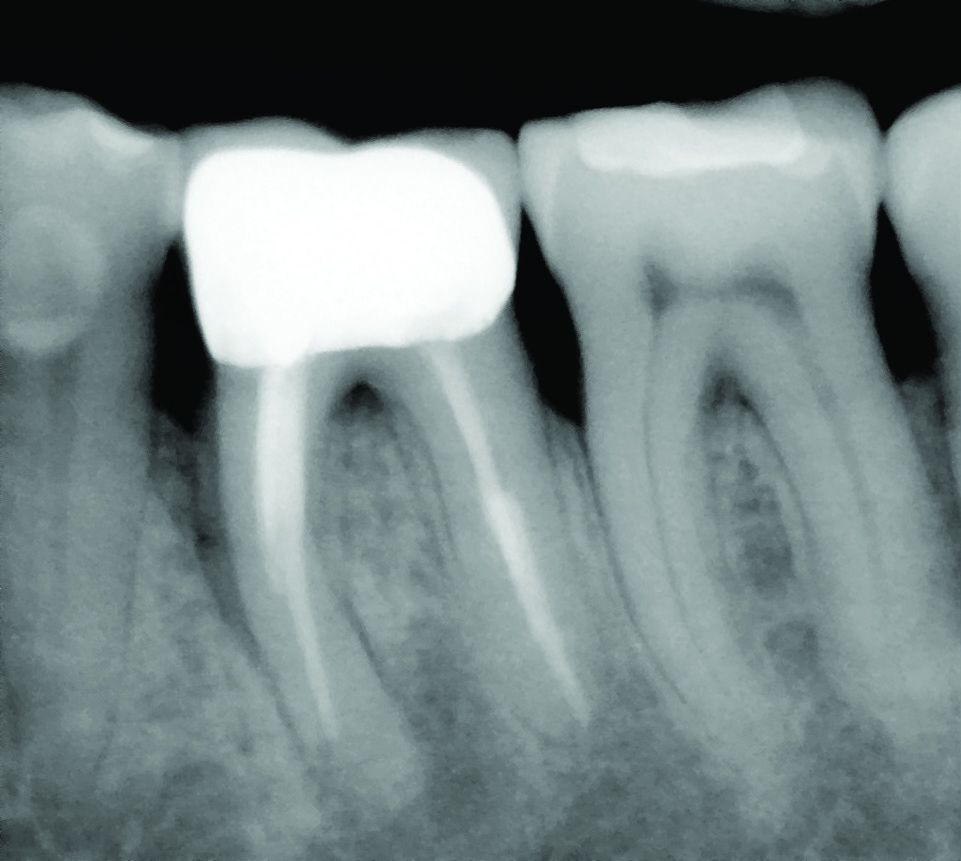

Such compromised conditions include vertically fractured roots, perforated roots, periodontally compromised roots due to furcation or root proximity issues, communicating endodontic-periodontal defects compounded by short root lengths, unresponsive furcation defects, significant untreatable external resorptive defects, and so on (Figure 1 through Figure 4). When conditions such as these affect single-rooted teeth, extraction is often the only way to eliminate the resultant pathology. With multirooted teeth, however, an additional option exists: definitively removing the cause of the pathology while simultaneously retaining the tooth in a functional state, which has published favorable survivability rates of upwards of 80% to 90%.1-3 If performed appropriately by taking into account the factors described in this article, this functional state can be maintainable for the long term, with a median survival time of 6 to 20 years.3-6

Fig 1. Examples of multirooted teeth showing periradicular periodontitis and loss of periradicular bone support isolated to one root (indicated by red arrows). Fig 1: Tooth No. 3 distobuccal root with circumferential bone loss from the crestal bone height to the apex with stable mesiobuccal and palatal roots. Fig 2: Tooth No. 30 with a prior apical surgery showing bone loss surrounding a fractured mesial root. Fig 3: Tooth No. 19 with lateral and apical bone loss regions affecting a fractured mesial root. Fig 4: 3D CBCT imaging of tooth No. 3 depicting an apicomarginal bone loss defect affecting the mesiobuccal root with stable fused distobuccal and palatal roots.

Fig 1 through Fig 4. Examples of multirooted teeth showing periradicular periodontitis and loss of periradicular bone support isolated to one root (indicated by red arrows). Fig 1: Tooth No. 3 distobuccal root with circumferential bone loss from the crestal bone height to the apex with stable mesiobuccal and palatal roots. Fig 2: Tooth No. 30 with a prior apical surgery showing bone loss surrounding a fractured mesial root. Fig 3: Tooth No. 19 with lateral and apical bone loss regions affecting a fractured mesial root. Fig 4: 3D CBCT imaging of tooth No. 3 depicting an apicomarginal bone loss defect affecting the mesiobuccal root with stable fused distobuccal and palatal roots.